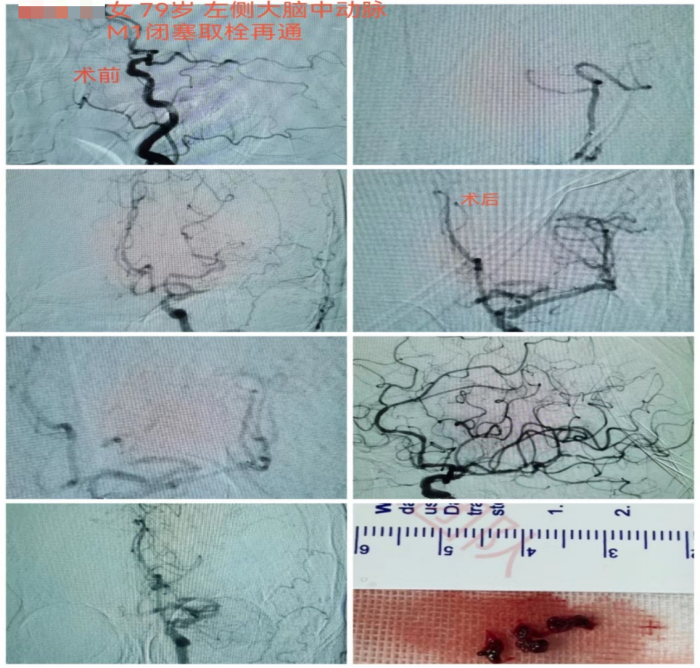

8月19日上午6时左右,家住天心区79岁的蒋奶奶因四肢乏力在客厅摔倒,家属扶起后症状未见好转,且无法言语。

9时左右,家属将蒋奶奶送至长沙市融城立博体育

,行头部CT和MRI后考虑左侧大脑中动脉闭塞引起的脑梗死,需立即接受动脉取栓治疗。长沙市融城立博体育

急诊,立即完善头颅CTA提示左侧大脑中动脉M1段栓塞。监测生命体征以及复查必要检查项目后,神经内科副主任医师冯铁桥与患者家属沟通病情及手术相关事项,签字后患者被转入早已做好准备的介入导管室,行“左侧大脑中动脉闭塞急诊介入开通术”,施行动脉取栓。

12时45分,患者被推进介入导管室,此时患者仍处于颅内大血管闭塞动脉取栓的黄金时间窗内(6小时),救治工作紧张有序地展开。10分钟后股动脉穿刺成功,患者的取栓血管通路顺利建立。

13时33分,患者闭塞的血管被开通,缺血的脑组织恢复有效的血流灌注。术后,患者血管再通良好,闭塞远端血流较前明显改善。患者右侧肢体肌力明显较发病时好转,能简单发声、听懂对话。

第二天,患者能自行下地行走,语言功能也得到恢复。从卒中发病到完成介入取栓治疗,蒋奶奶的“生死时速”过程历经6小时40分钟。